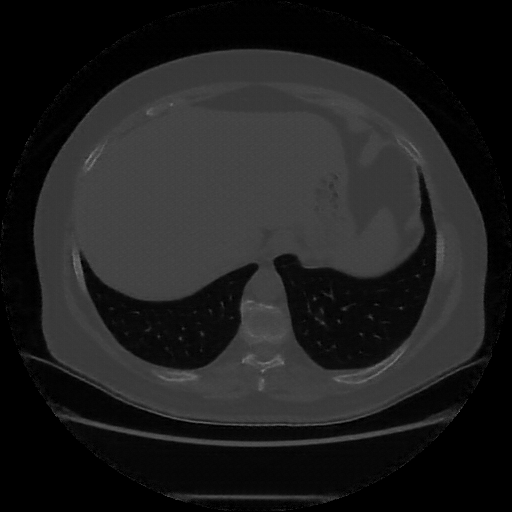

Generated VENOUS CT scan (A→B translation)

Lung window (WL -600, WW 1500 β†’ Low βˆ’1350, High +150)